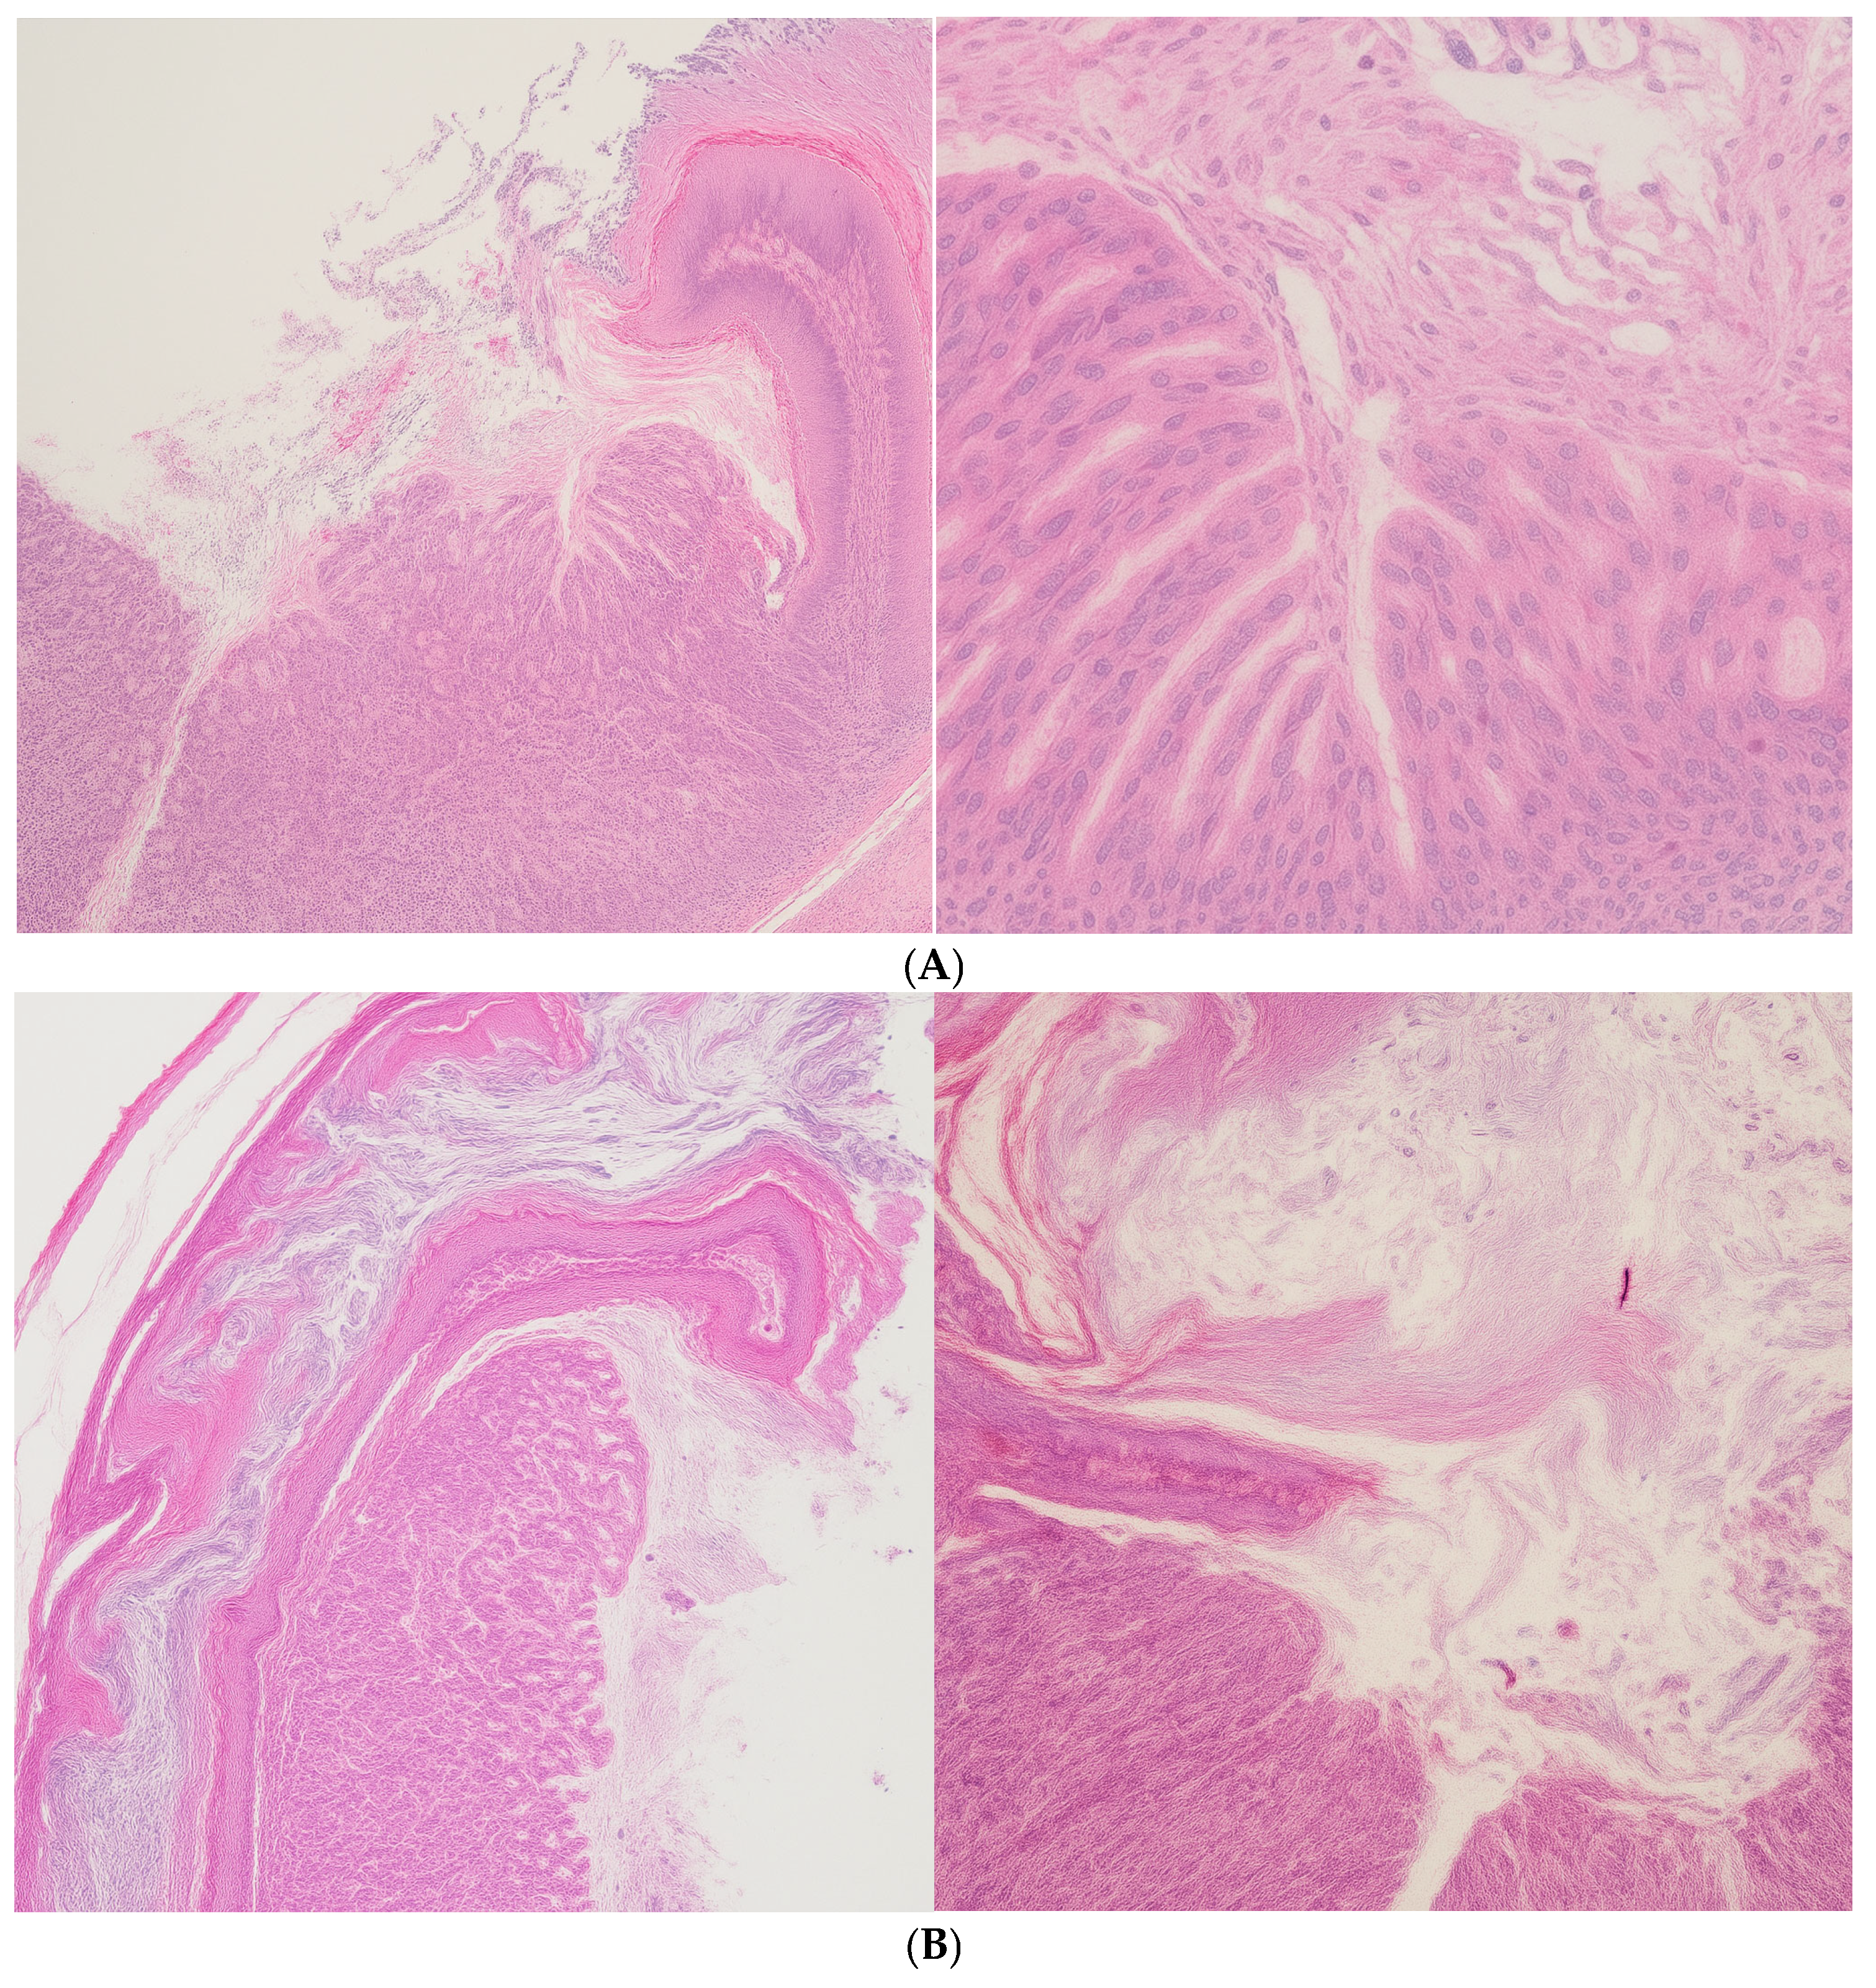

In the spleen, both the 10 mg/kg and 20 mg/kg groups preserved normal histological architecture (

Figure 1A). Active extramedullary hematopoiesis was present, involving erythroid, myeloid, and megakaryocytic precursors, which is consistent with physiological activity in murine spleen tissue. In contrast, the 50 mg/kg group exhibited multifocal amyloid deposits in the perifollicular zones (

Figure 1B). These deposits led to the compression and focal atrophy of adjacent splenic tissue, suggesting a dose-related accumulation of proteinaceous material potentially associated with nanoparticle clearance or chronic immune activation.